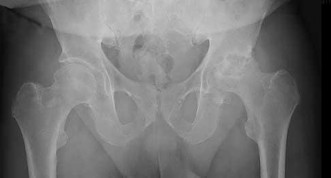

A 32-year-old male is brought to the trauma bay in hemorrhagic shock after a motorcycle crash. An anteroposterior radiograph of the pelvis demonstrates an APC-III injury. A pelvic binder is applied. To maximize reduction of the pelvic volume, at what anatomical landmark should the binder be centered?

Correct Answer: Greater trochanters

Explanation:

Pelvic binders should be centered over the greater trochanters to effectively close the pelvic ring and reduce pelvic volume. Placement over the iliac crests or ASIS can paradoxically widen the true pelvis or fail to achieve adequate reduction in an open-book pelvic injury.